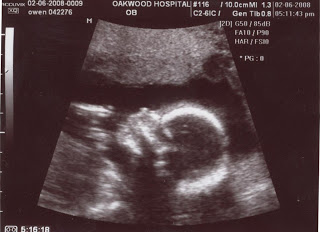

I realize all ultrasound pictures tend to look the same and I’m sure these are no exception. However, we had to laugh at Ruby’s smile at the end of her photo session.

No smile…